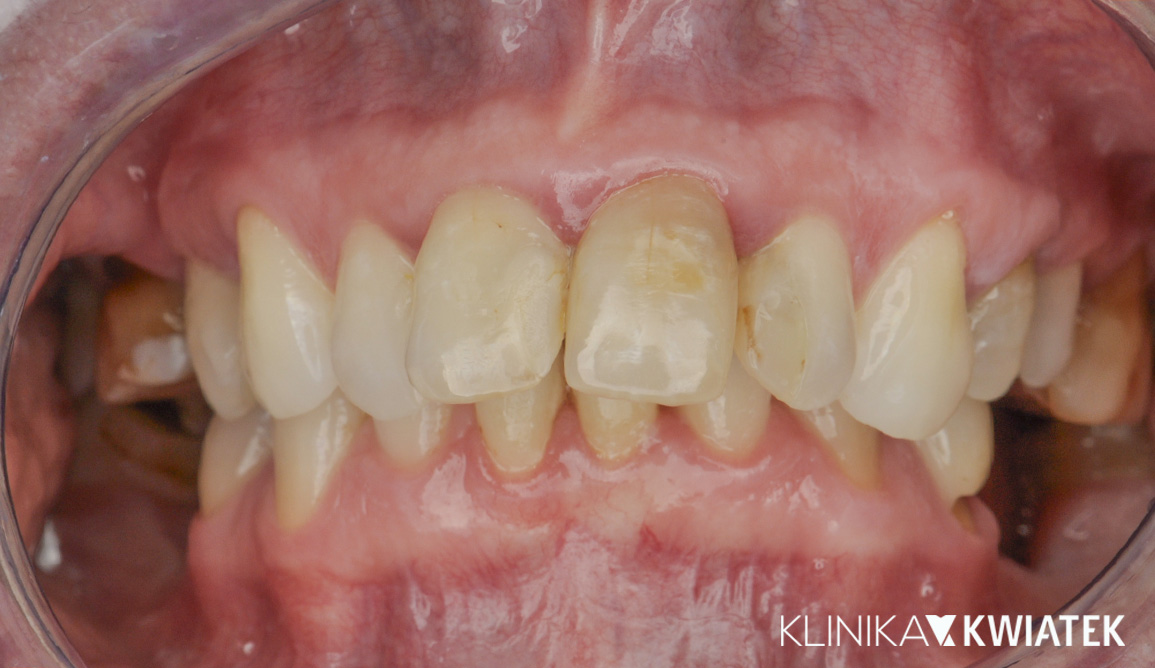

PRZED

PO